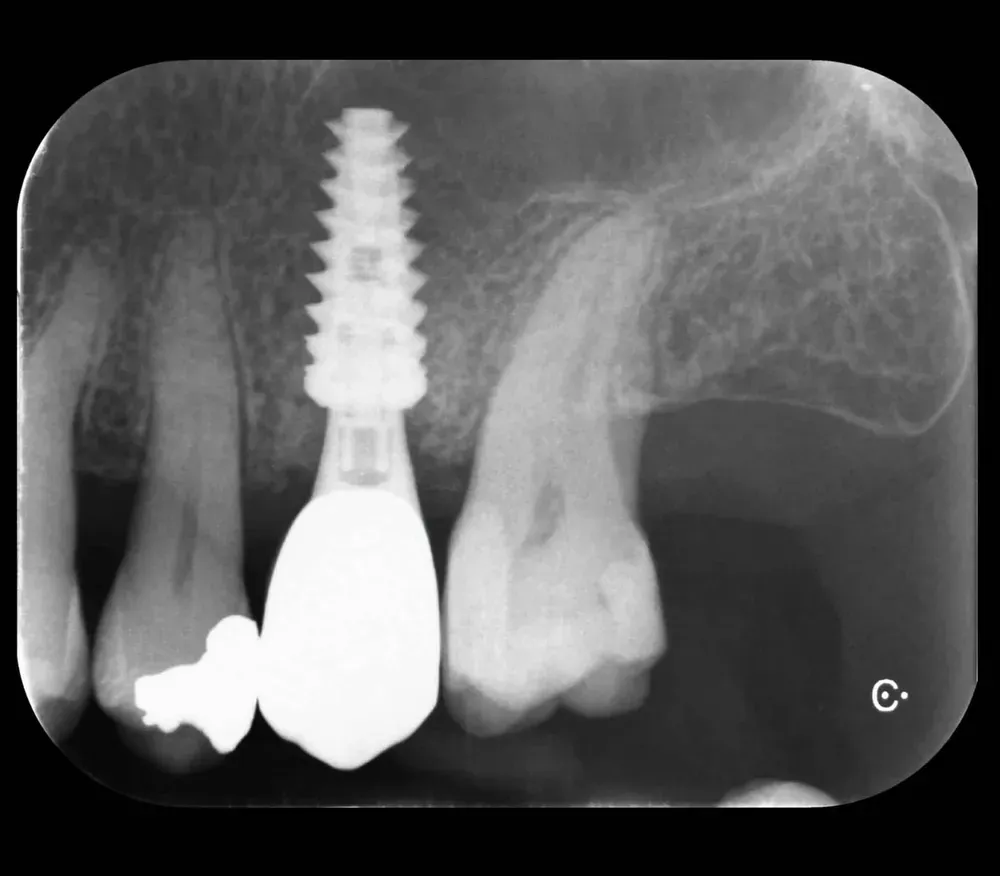

Per concludere il confronto tra le varie connessioni, l’immagine che segue è una radiografia con due impianti affiancati: un tissue-level ben posizionato fatto da un collega anni addietro e un impianto a connessione conica in posizione infracrestale con abutment della corretta lunghezza per il caso. Il secondo è un mio caso. È interessante notare come il cono dello spazio biologico sia identico. Se ben posizionati, tutti gli impianti funzionano egregiamente (l’impianto più vecchio inizia a soffrire un pochino, ma questa è un’altra storia).

Saper leggere la radiografia

Chi ha l’occhio allenato sa che il destino di un impianto è spesso scritto già nelle radiografia post-operatoria. Si vedono i punti dove la struttura non calza. Dove le tensioni meccaniche sono eccessive. Dove il collega ha forzato con il cacciavite per fare entrare la protesi.

In quelle zone la biologia non perdona: la tensione si traduce in riassorbimento osseo, e lo spazio non sigillato diventa il nido perfetto per i batteri (l’osseointegrazione è un equilibrio delicato). Gli anaerobi gram-negativi, i nostri nemici, amano questi spazi chiusi, lontani dalla luce, dall’ossigeno e dal sangue. Per chi sa interpretare questi segnali, la peri-implantite futura non è un’ipotesi. È una diagnosi anticipata.